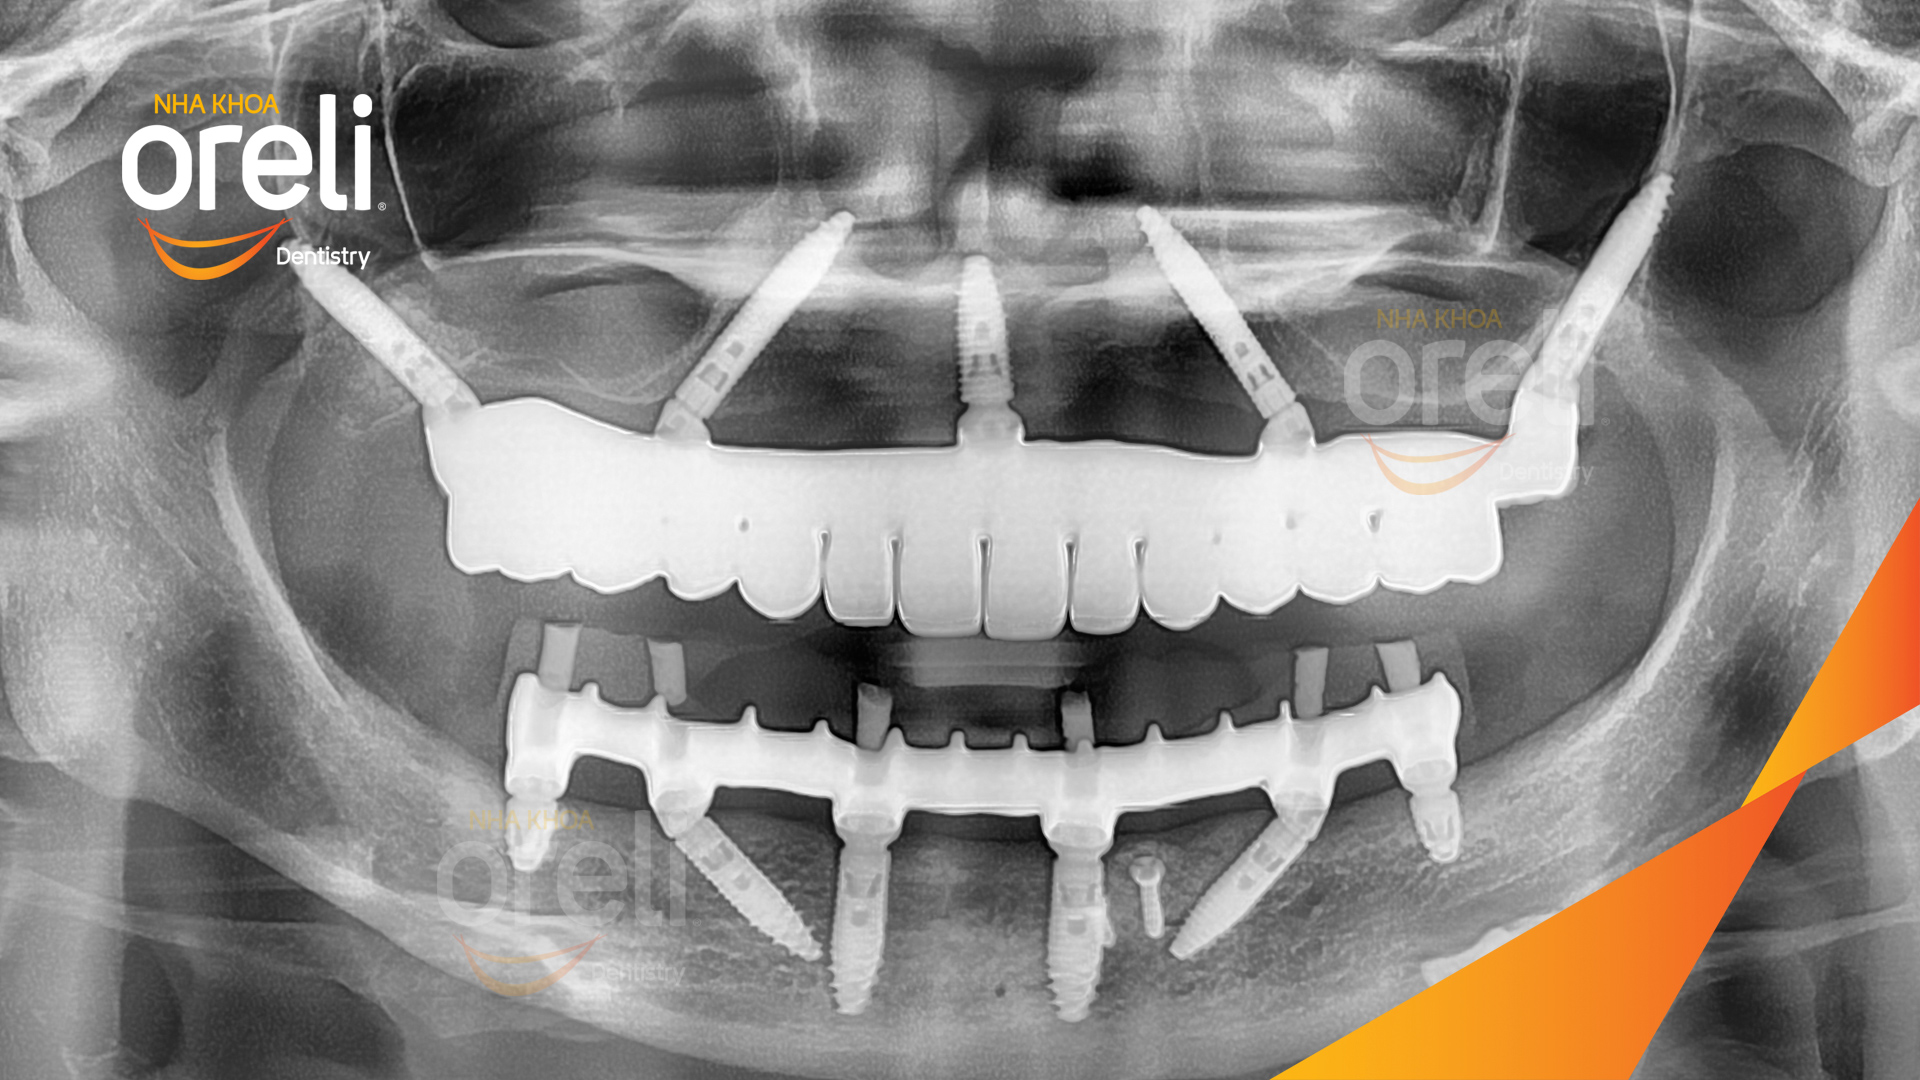

Giải pháp: Cắt bỏ cầu sứ nhổ răng lung lay, cấy ghép răng implant hàm trên và dưới

Thời gian: 2 tuần

Kết quả: Chị khách cười nói tự tin và ăn nhai chắc chắn

Hình ảnh thực tế